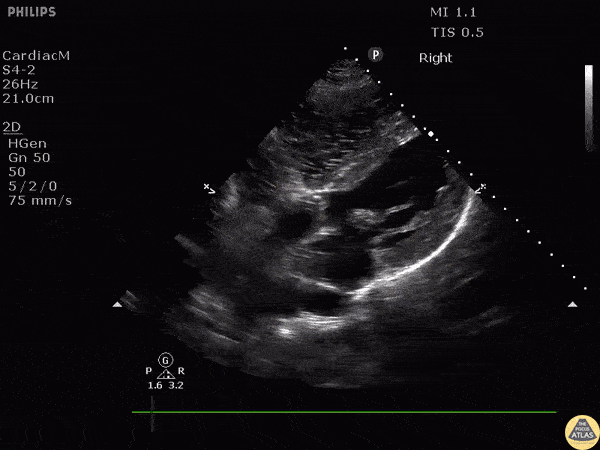

Left Ventricular Dysfunction - Ventricular Fibrillation

Subcostal view of a patient reentering ventricular fibrillation following ROSC. Image courtesy of Robert Jones DO, FACEP @RJonesSonoEM Director, Emergency Ultrasound; MetroHealth Medical Center; Professor, Case Western Reserve Medical School, Cleveland, OH View his original post here